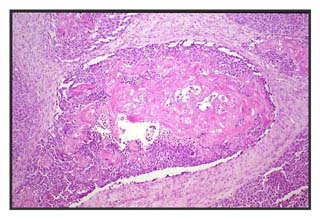

Figura 2: Nidos sólidos de células basalioides con necrosis central y carácter infiltrante.